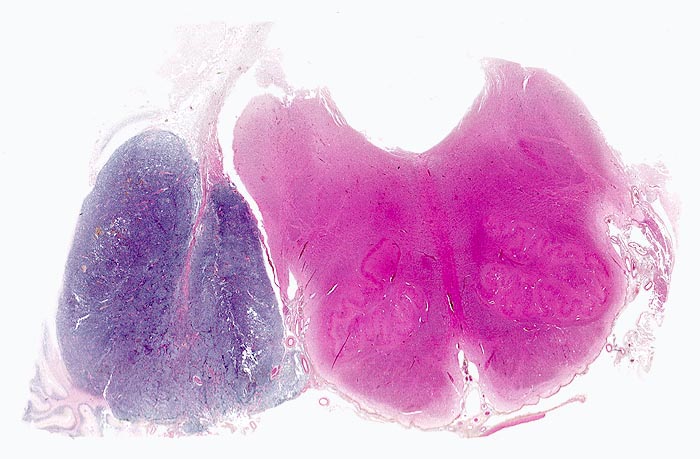

Wegen der hohen Zelldichte und der hohen Kern-Zytoplasmarelation erscheinen die Tumoren in der HE Färbung blau. Medulloblastome müssen differentialdiagnostisch von morphologisch ähnlichen kleinzelligen undifferenzierten Karzinomen und Lymphomen abgegrenzt werden. Das klassische Medulloblastom besteht aus dicht gepackten Zellen mit runden bis ovalen oder karottenförmigen stark hyperchromatischen Kernen umgeben von wenig Zytoplasma. Runde Zellen mit weniger dichtem Chromatin sind oft beigemischt. Zahlreiche Mitosen, flächenhafte Nekrosen und Apoptosen sind typisch. In weniger als einem Drittel der Fälle findet man die typischen Homer-Wright Rosetten. Diese bestehen aus ringförmig angeordneten Tumorzellkernen um ein fibrilläres Zentrum aus Zytoplasmafortsätzen.

• Scharf begrenzter rundlicher sehr zellreicher (deshalb blauer) Tumor.

• Monomorpher Zellrasen mit hyperchromatischen ovalen oder karottenförmigen Zellkernen.

• Kaum erkennbares Zytoplasma.

• Homer-Wright Rosetten aus ringförmig angeordneten Tumorzellkernen um ein fibrilläres Zentrum aus Zytoplasmafortsätzen.